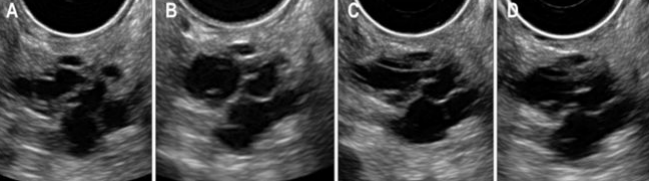

Describe this mass

Dx?

A large, ill-defined, hypoechoic, complex mass located within the pancreatic tail.

Dx: most likely cystic adenocarcinoma but requires biopsy

Describe this image

A large, hypoechoic, complex mass with both solid and cystic components.

Dx: pancreatic adenocarcinoma with cystic mass